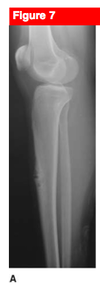

12 yo male comes in with fever, and painful left hip. Below is his XR. Diagnosis? Managment? Treatment?

Ewing Sarcoma

-

Differential

- infection

- leukemia

- osteosarcoma

- neuroblastoma (if young)

-

Radiology

- permative, moth eatten appearance

- diffuse, aggressive, lytic lesion with periosteal reaction

- may be evidence of onion skinning or sunburst

- ill defined margins, associated soft tissue mass